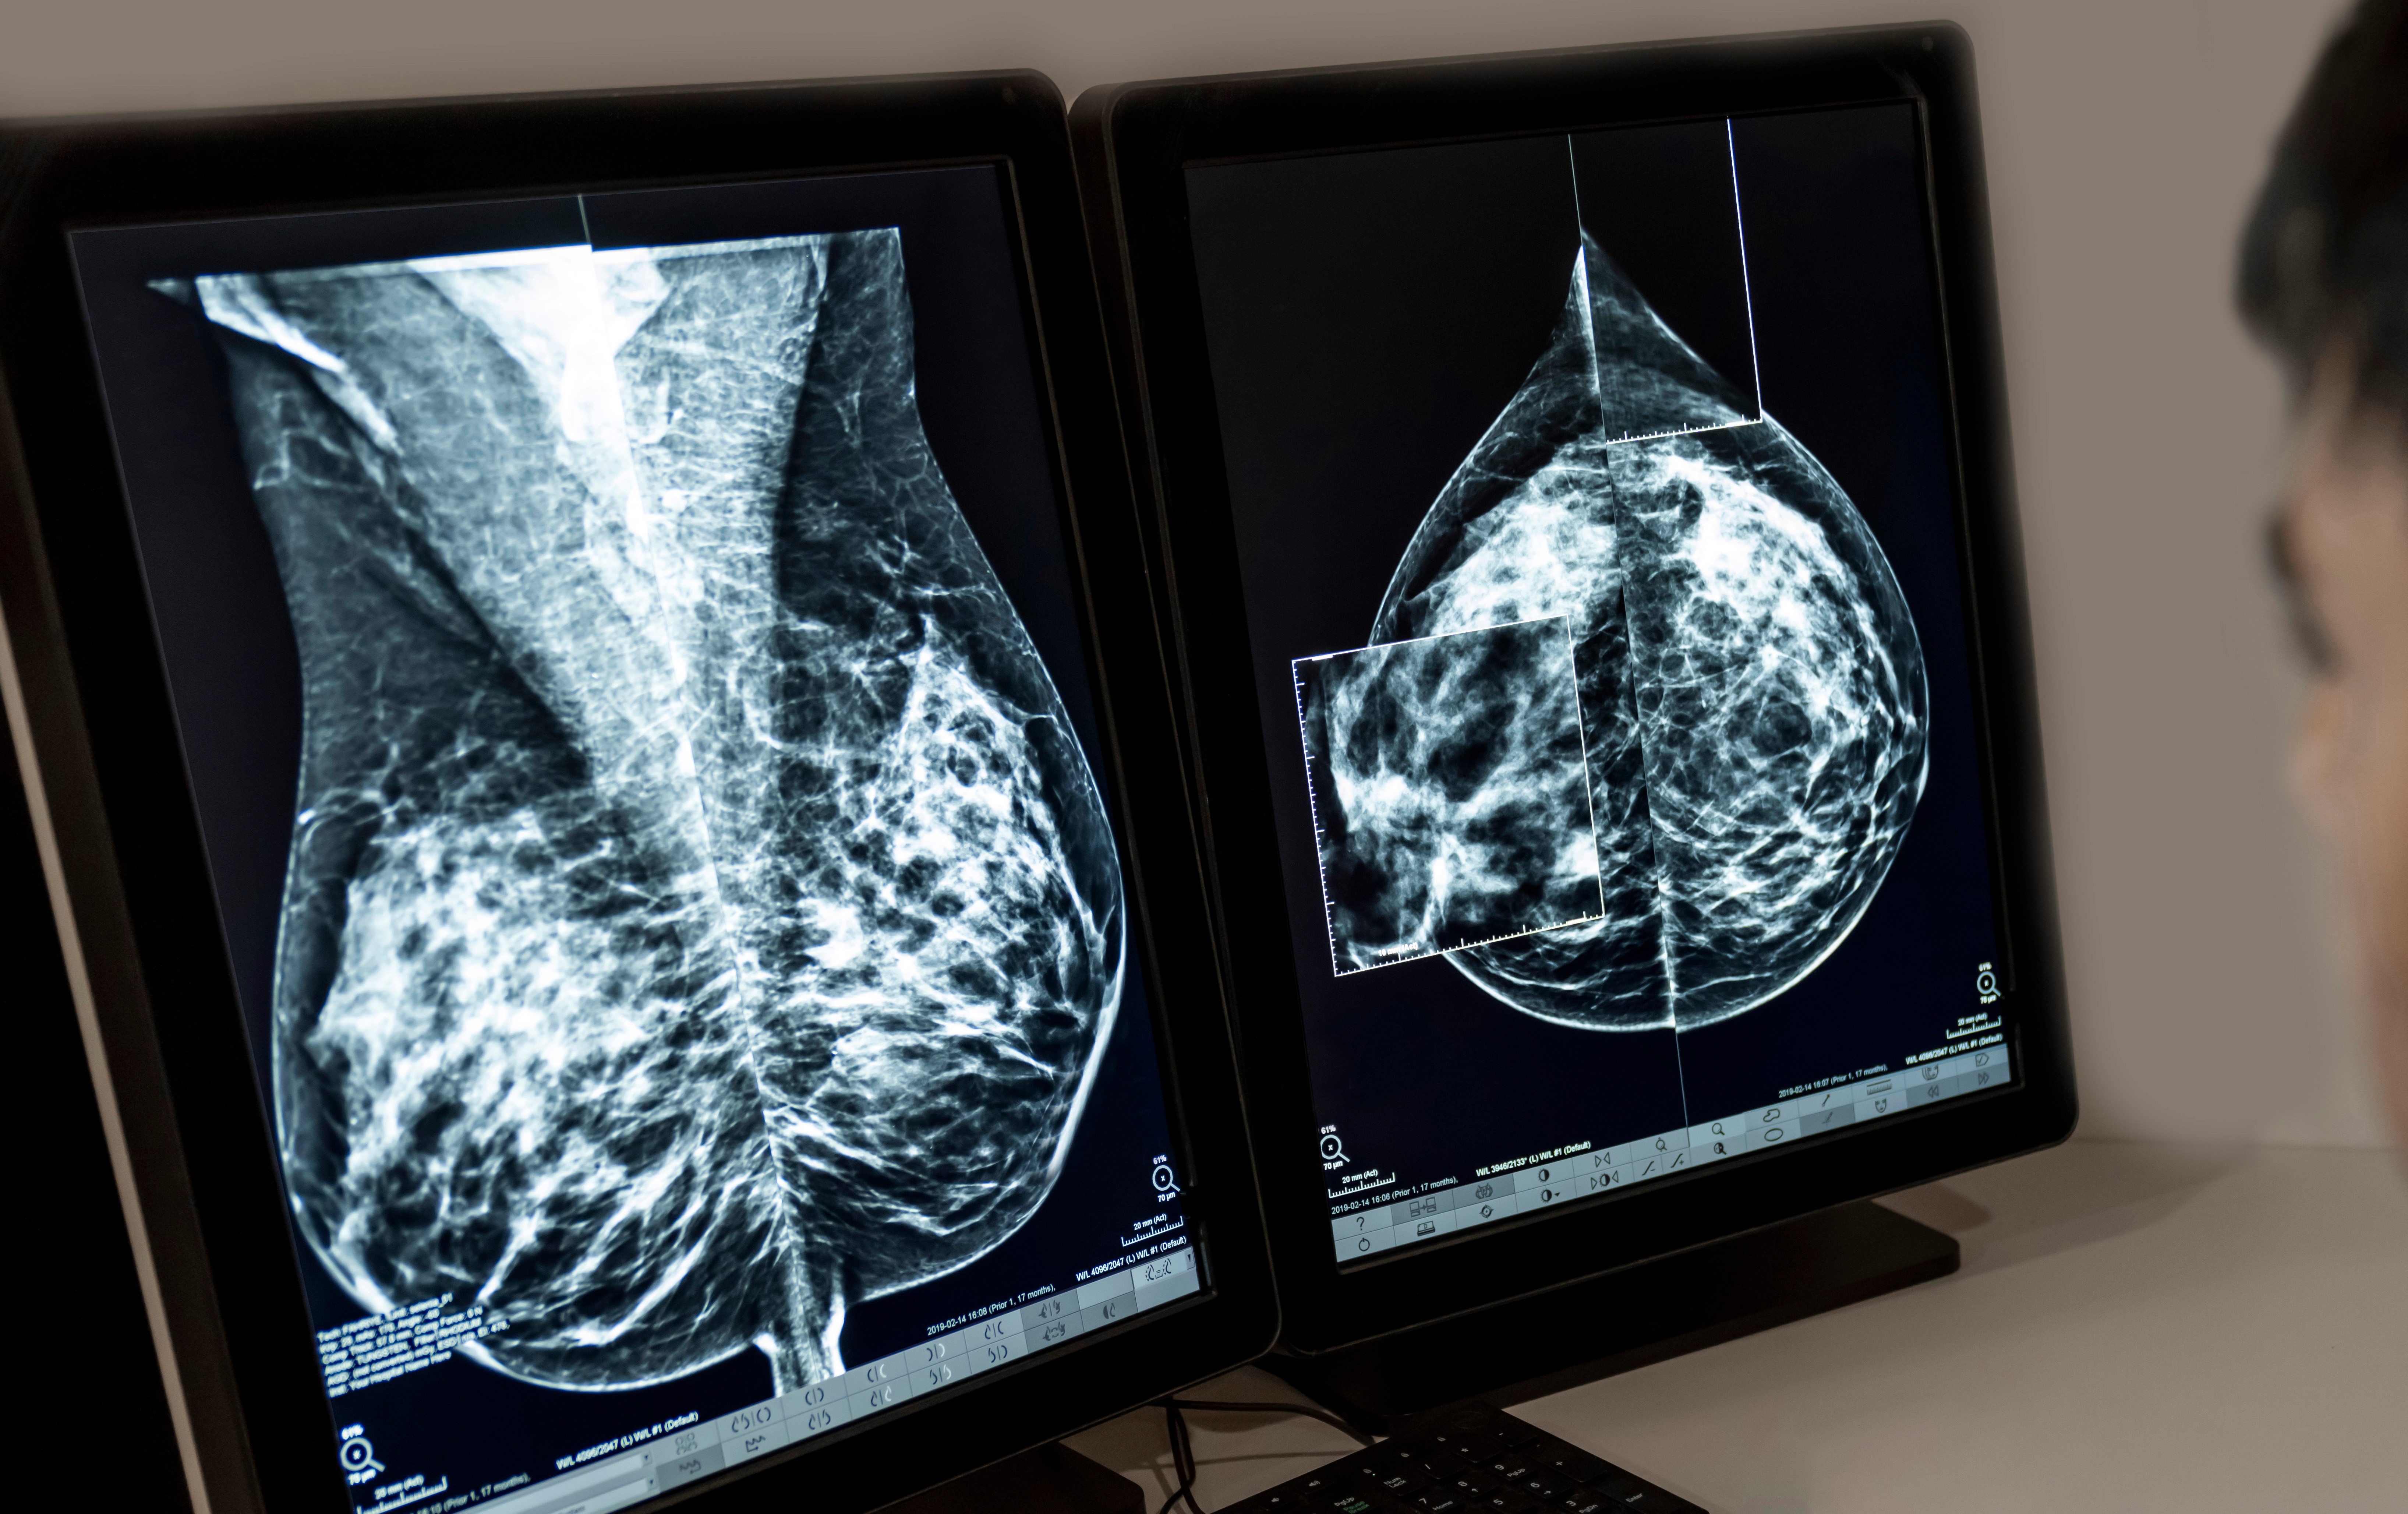

RJ tem a segunda maior mortalidade por câncer de mama no país, diz Inca

03/10/2025 - Segundo o Inca, o RJ tem a segunda maior mortalidade por câncer de mama no país

Adobe Stock

O Estado do Rio de Janeiro possui a segunda maior taxa de mortalidade de mulheres vítimas de câncer de mama por 100 mil habitantes no país com 16,5 casos. Os dados, referentes ao ano de 2023, foram divulgados nesta sexta-feira (3) pelo Instituto Nacional do Câncer, durante o lançamento da campanha Outubro Rosa. Roraima lidera o ranking de mortalidade.

O número de casos registrados no RJ também é o segundo maior do país, com 70,57 casos de câncer de mama por 100 mil habitantes entre 2023 e 2025. O maior número é de Santa Catarina.

“É fundamental investirmos na prevenção. Controle de peso, evitar tabagismo e consumo de álcool. E é importante o rastreio entre mulheres entre 50 e 74 anos de idade e podendo ser oferecido para mulheres com idade entre 40 e 49 anos”, afirmou Braga.

“Hoje temos menos de 30% das mulheres em idade alvo ainda fazendo a sua mamografia a cada dois anos entre 50 e 74 anos de idade, mostrando que uma parte ainda não consegue fazer a mamografia”, disse o coordenador.

“Um ponto importante e dois cenários: temos mamografias sobrando no Rio Imagem Machado e no Rio Imagem Centro. Por outro lado, quando temos um equipamento complementar, que é o mamógrafo móvel, vemos uma espera grande de mulheres e quando o equipamento vai próximo, conseguimos chegar a elas”, finalizou Braga.